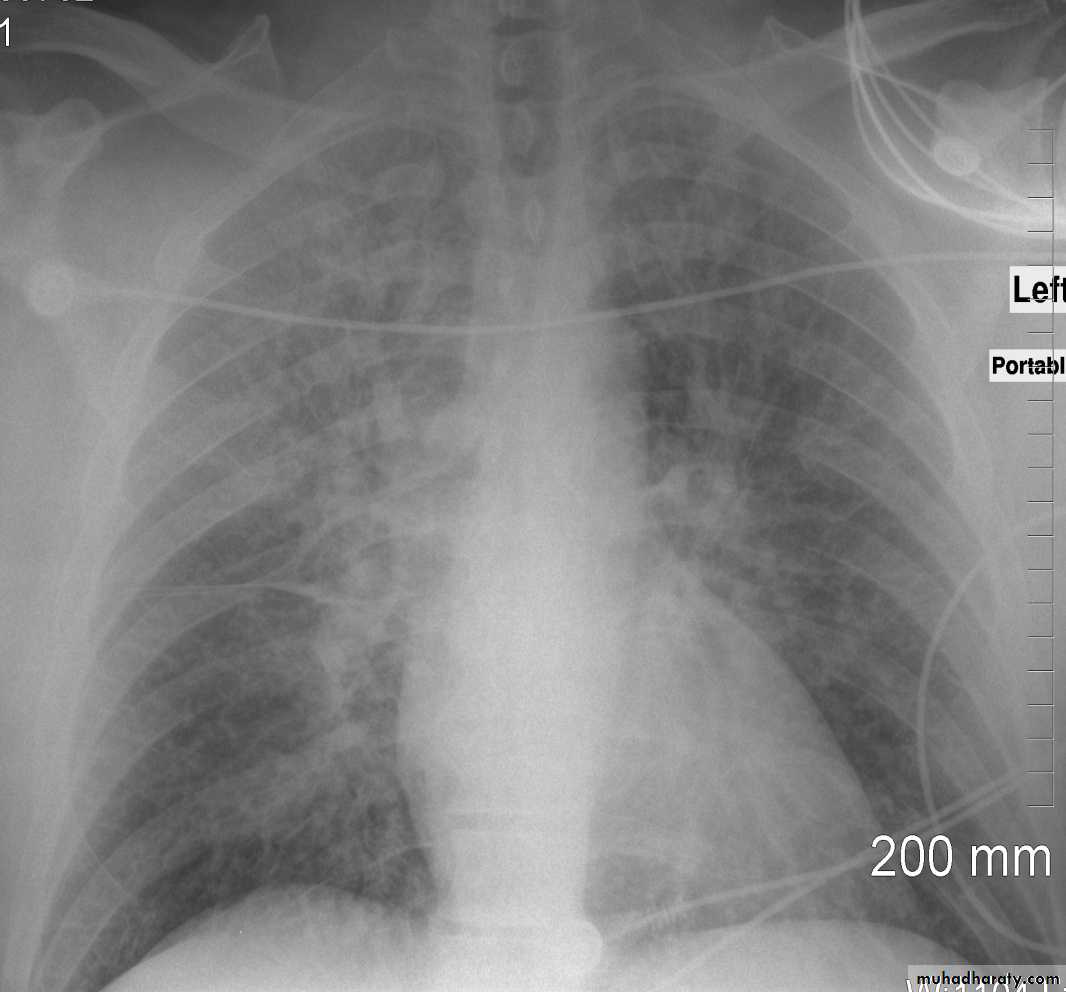

With left sided congestive cardiac failure, the features are that of pulmonary edema which includes:

central pulmonary venous congestion ( prominent hilum )

cephalisation of pulmonary veins ( upper lobe pulmonary venous diversion )

(Septal lines) pulmonary interstitial oedema

pulmonary alveolar oedema

Cardiomegaly

Pleural effusion

radiograph include if pressure > 25 mmHg the findings of :

1.cardiac size/cardio-thoracic ratio: useful for assessing for an underlying cardiogenic cause or association2.Pulmonary Alveolar edema: bat wing pulmonary opacities

3.Pulmonary interstitial edema: presence of peri-bronchial cuffing///septal lines: Kerley lines become more prominent4.pleural effusions

5.Central pulmonary venous engorgement

6.pulmonary blood flow distribution& upper lobe pulmonary venous diversion

Alveolar pulmonary edema